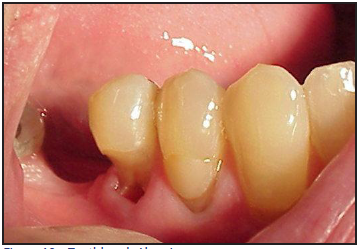

Abrasion and recession

Tooth and gingival abrasion are defined as pathologic wear as a result of a foreign substance (Figure 10). Abrasion is multi-factorial but is generally believed to be caused by over-zealous toothbrushing. Studies have also reported an increase in cervical lesions in people who brush with greater frequency, for longer periods of time and use the "scrubbing" brushing technique.34,35

Figure 10 – Toothbrush Abrasion

Figure 10